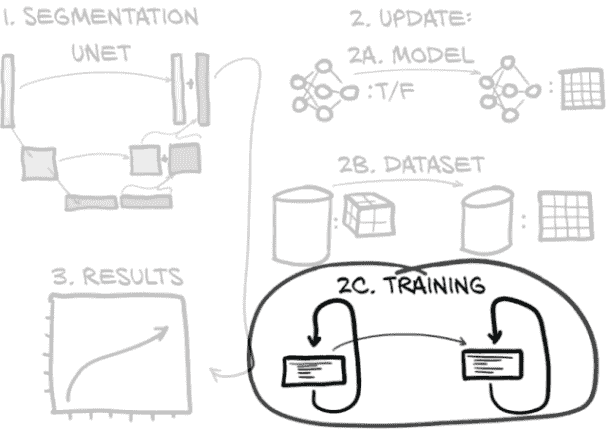

这意味着我们仍然专注于与第十一章相同的图 12.1 的同一部分。但现在我们正在努力使我们的分类模型工作良好而不是只是工作。本章重点讨论如何衡量、量化、表达,然后改进我们的模型执行工作的能力。

图 12.1 我们的端到端肺癌检测项目,重点放在本章的主题上:第 4 步,分类

到本章结束时,我们将创建一个新模型,其架构可以执行像素级标记,或分割。完成这项任务的代码将与上一章的代码非常相似,特别是如果我们专注于更大的结构。我们将要做出的所有更改都将更小且有针对性。正如我们在图 13.2 中看到的,我们需要更新我们的模型(图中的第 2A 步),数据集(2B),以及训练循环(2C),以适应新模型的输入、输出和其他要求。(如果你在图中右侧的步骤 2 中不认识每个组件,不要担心。我们在到达每个步骤时会详细讨论。)最后,我们将检查运行新模型时得到的结果(图中的第 3 步)。

图 13.2 用于分割的新模型架构,以及我们将实施的模型、数据集和训练循环更新

将图 13.2 分解为步骤,我们本章的计划如下:

-

分割。首先,我们将学习使用 U-Net 模型进行分割的工作原理,包括新模型组件是什么,以及在我们进行分割过程中会发生什么。这是图 13.2 中的第 1 步。

-

更新。为了实现分割,我们需要在三个主要位置更改我们现有的代码库,如图 13.2 右侧的子步骤所示。代码在结构上与我们为分类开发的代码非常相似,但在细节上有所不同:

-

更新模型(步骤 2A)。我们将把一个现有的 U-Net 集成到我们的分割模型中。我们在第十二章的模型输出一个简单的真/假分类;而在本章中的模型将输出整个图像。

-

更改数据集(步骤 2B)。我们需要更改我们的数据集,不仅提供 CT 的片段,还要为结节提供掩模。分类数据集由围绕结节候选的 3D 裁剪组成,但我们需要收集完整的 CT 切片和用于分割训练和验证的 2D 裁剪。

-

调整训练循环(步骤 2C)。我们需要调整训练循环,以引入新的损失进行优化。因为我们想在 TensorBoard 中显示我们的分割结果的图像,我们还会做一些事情,比如将我们的模型权重保存到磁盘上。

-

-

结果。最后,当我们查看定量分割结果时,我们将看到我们努力的成果。